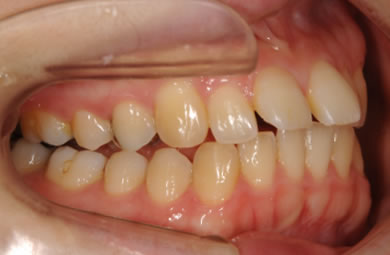

| 性別/年齢 | 女性 / 24歳 | ||||||||||||||||||||||||||||||||

| 主訴 | 矯正治療を希望し治療方針を相談する為、来院。 | ||||||||||||||||||||||||||||||||

| 治療方針 | 舌が横にはみでて、上下の歯が全く咬んでいない状態です。口元はきれいなので、歯は抜かずに歯列を少し横に広げて並べます。ゴムを使用したり、舌を訓練したりとても協力が必要な症例です。 | ||||||||||||||||||||||||||||||||

| 治療内容 | 唇側矯正(ホワイト)、保定装置 | ||||||||||||||||||||||||||||||||

| 総治療費 | 721,000円 | ||||||||||||||||||||||||||||||||

| 治療期間 | 9ヶ月 |